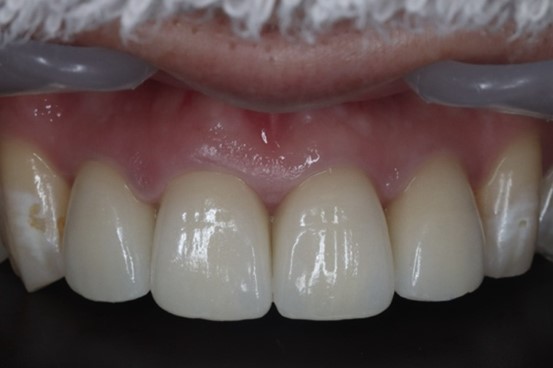

目白マリア歯科|【症例】自然な美しさを考慮した審美歯科治療|最終補綴物装着後2週間後

既存の前歯部の被せものを外し、仮歯を調整してかみ合わせに問題がないかを診査しました。その上で最終補綴物の製作を行いました。

今回最終補綴物として選択したマテリアル(材料)はオールセラミッククラウンです。

オールセラミッククラウンは、陶材で作られているため光の透過度が天然歯に似ていることから、装着後の違和感が少ないのが特徴です。

また、ステイン、プラークが付着しにくく、歯ぐきへの負担も少ないことで知られています。

かみ合わせの調和と、周りの天然歯と馴染む色の仕上がりにすることで、審美的回復を機能面と見た目を両立して実現しました。

治療後の様子

目白マリア歯科|【症例】自然な美しさを考慮した審美歯科治療|治療後の口腔内写真

歯肉の状態は非常に健康な状態に保たれ、かみ合わせも仮歯製作時と同様に良好です。